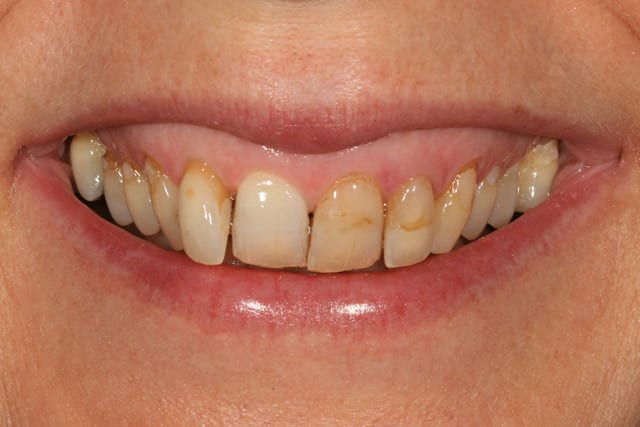

cette patiente que je suis en controle depuis 2 ans, se décide à faire quelque chose pour son sourire.

grosso modo depuis 2 ans, pas de soucis particuliers, pas de caries, faut faire un peu gaffe à la paro mais elle est plutôt motivée et ça se passe bien.

elle a plein de vieux compos d'une mauvaise couleur, au joints colorés, des dents de couleur pas vraiment toutes pareilles ; et un sourire très gingival.

je ne sais pas trop d'ou ça viens, de mylolyses traitées au compo ou d'un épisode de caries au collet ?

elle ne fume pas, bois du thé, un peu de café.

elle a certes un sourire très gingival lié à la classe II, mais est-ce si grave que ça ?

et du point de vue esthétique, le gummy smile est il une hérésie ?

peut on selon vous envisager un traitement esthétique qui ne cherche pas forcément à corriger ce critère ?